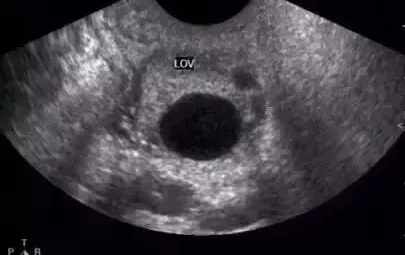

正常成熟的優勢卵泡的聲像圖

?、?卵泡最大直徑達20mm,優勢卵泡最大直徑范圍為17~24mm,體積2.5~8.5mm³。徑小于17mm者為非成熟卵泡。

② 卵泡外形飽滿呈圓形或橢圓形,內壁薄而清晰,或可見內壁卵丘所形成的一金字塔形的高回聲,多在排卵前24~30小時易于顯示。亦可見優勢卵泡周圍有一低回聲暈(多由排卵前卵泡膜組織水腫所致)。

?、?卵泡位置移向卵巢表面,且一側無卵巢組織覆蓋,并向外突出。

卵泡的聲像表現為圓形或橢圓形無回聲區,位于卵巢皮質內,邊界清晰,囊壁菲薄,內壁光滑。在月經的早期,卵巢皮質內可見多個直徑3~5mm的小卵泡,隨著月經周期的推移,卵泡逐漸增大,形成優勢卵泡,而其它小卵泡逐漸萎縮。主導卵泡成熟,逐漸突出于卵巢表面。對卵泡的觀察除注意其形態、數目、回聲外,測量卵泡的大小對了解其生長發育狀態、藥物治療效果以及判斷卵泡成熟是十分重要的。